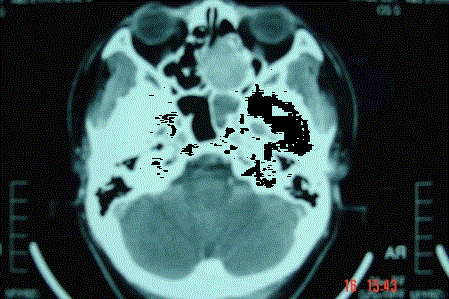

问题 病历摘要: 患者男,37岁,因右鼻塞伴涕中带血4个月入院,患者4个月前始右鼻塞,为间断性,偶有涕中带血,时有流脓性分泌物,并症状渐渐加重。但发病以来患者无头痛、面部麻木和疼痛,无复视及流泪,张口正常。检查:右侧鼻腔总鼻道可见表面光滑、质中、粉红色肿物,触之不易出血。鼻咽黏膜光滑,未见新生物和黏膜糜烂。颈部未及淋巴结肿大。 按UICC1992年分期,该患者为: 提示:通过病理活检,结果为囊性腺样癌